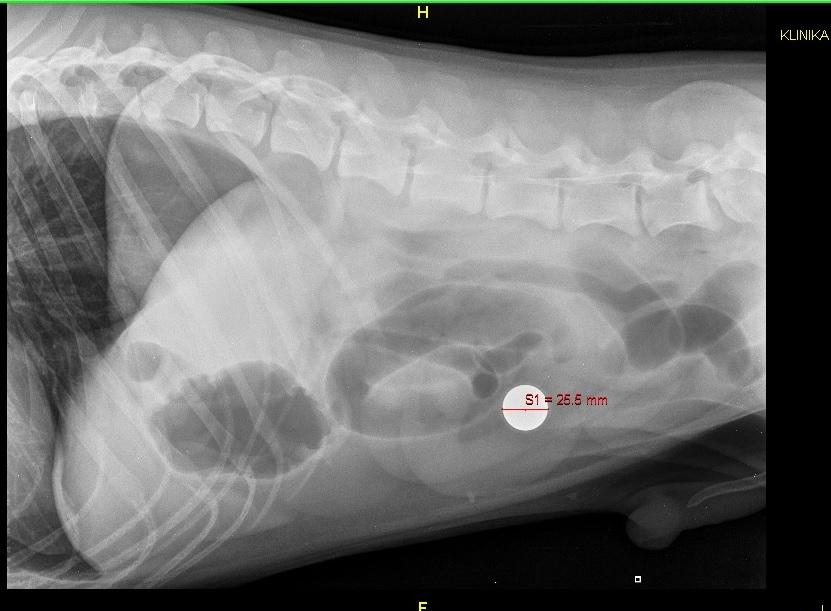

3. Witam, dzisiaj mój kochany pies przeszedł zabieg z powodu niedrożności jelit. Po zrobieniu zdjęcia rtg myśleliśmy z weterynarzem, że połknął jakąś monetę. Weterynarz długo się męczył, żeby znaleźć w brzuszku ciało obce, aż w końcu udało mu się wyciągnąć ciężką kulkę. Wydawało mi się, że jest to kulka od starych myszek ponieważ one też były ciężkie i osłonięte gumą jednak gdy wróciłam do domu wygrzebałam z szafy starą myszkę i szybko okazało się, że kulka, którą połknął jest większa. Ktoś z Was ma pomysł co to takiego jest? Może to jednak kulka od myszki, jakiś inny typ? Jeśli tak to orientujecie się jaki metal jest w środku? Dołączam zdjęcia, Pozdrawiam K ;)

2. Ta obok do porównania to właśnie ta kulka, którą wyjęłam z myszki. Właśnie zastanawiałam się, że może ta, którą znalazł i połknął jest z jakiejś myszki innego typu, ale jednak wydaje mi się, że te kulki są uniwersalne jednakowej wielkości niezależnie od wielkości myszki w każdym razie chciałam się zapytać o to Was bo mi już nic nie przychodzi do głowy. Piesek nadal otumaniony. Zabieg miał o 15:30 do około 17. Od tamtej pory spał i teraz próbował wstać choć nadal nie ma siły.Leżał cały czas na boku teraz lekko zgarbiony położył się na brzuch i troche się martwie żeby przez to nie naruszył sobie zszytego jelita. Może macie dla mnie jakieś rady? Wybaczcie, że zawracam głowę, ale piesek to moje oczko w głowie i jestem przerażona chyba bardziej od niego...;)